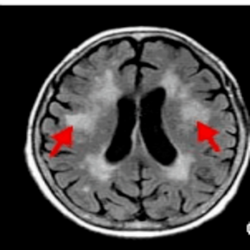

Fluid-attenuated inversion-recovery (FLAIR) image from individual with demyelinating disease (arrow indicates lesion)